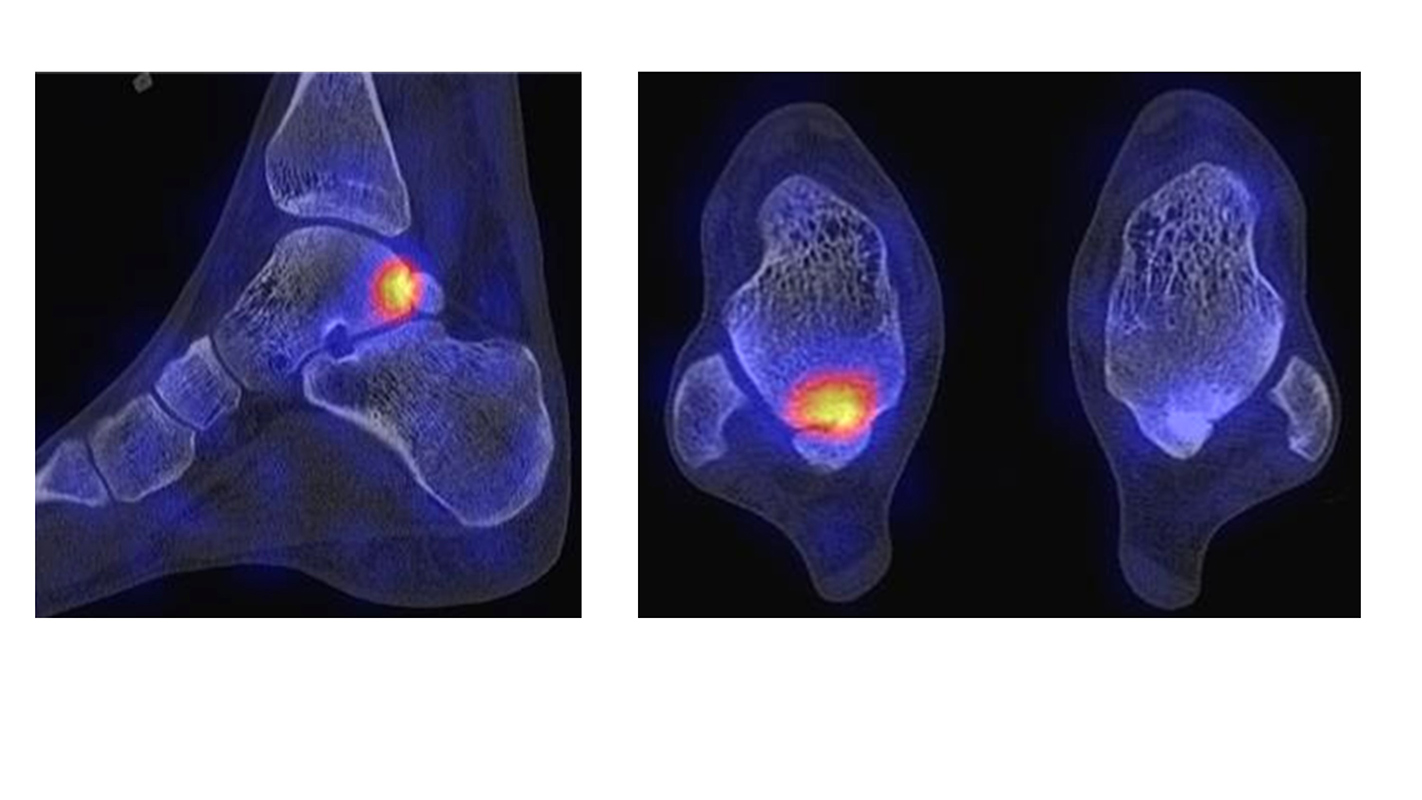

Abbildung 9.2.a bis d: SPECT/CT zur Beurteilung der Knochen-Vitalität bei einer Talusnekrose. 5 Jahre zuvor während der Arbeit war die Patientin beim Treppensteigen umgeknickt und zog sich Außenbandrupturen zu. Nachfolgend persistierende Beschwerden mit Entwicklung einer Talusnekrose. Frage nach Vitalität und Ausdehnung der Nekrose. Deutliche bis intensive Traceranreicherung im Bereich des linken Talus. Im SPECT/CT befindet sich der Hypermetabolismus in allen Abschnitten des Talus mit relativer Aussparung eines sich demarkierenden Fragmentes lateral, was die laterale Talusschulter umfasst, die Größe beträgt transversal ca. 23 x 16 mm. In diesem Fragment relativ homogene Skelettstruktur, diese Befunde weisen auf eine trophische bzw. nekrotische Störung des Talus hin mit einem sich demarkierendem Fragment, welches die laterale Talusschulter beinhaltet.

Die Abbildung 9.3.a bis d zeigt ein weiteren Fall mit einer SPECT/CT zur Beurteilung der Knochen-Vitalität bei einer Talusnekrose. Die Bilder zeigen eine abgelaufene Nekrose mit zystischen Resorptionen des linken Talusdoms bei nachweislich erhaltener Vitalität der umgebenden Knochenabschnitte aufgrund des hier überall deutlich erhöhten Knochenmetabolismus (= inkomplette Restitutio). Aufgrund der nachweislich erhaltenen Vitalität konnte erfolgreich eine Knochen-Transplantation erfolgen.Deutlich geringer ausgeprägte nekrotische Veränderungen auch im rechten Talusdom bei hier weitgehend erhaltenen Gelenkkonturen.